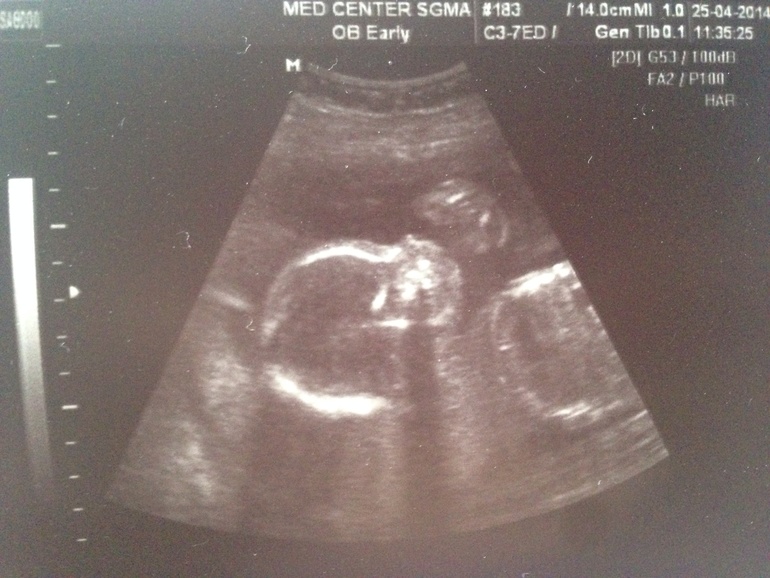

Узи 21 неделя +фото!

Результаты: УЗИ, КТГ, доплера, скринингаВыдохнули мы с мужем с облегчением, все отлично и хорошо! Единственное бедрышко у нас 32,3 а надо 35-37 вроде, но мы с мужем невысокие, так что врач сказал , что это в полне нормально уже на таком сроке. Так что мы счастливы, бодры и здоровы! 2 дня подряд на природе отдыхаем с утра до вечера, малышу так походу нравится, что на время прибывания на воздухе он затихает, только сажусь в машину начинается футбол.